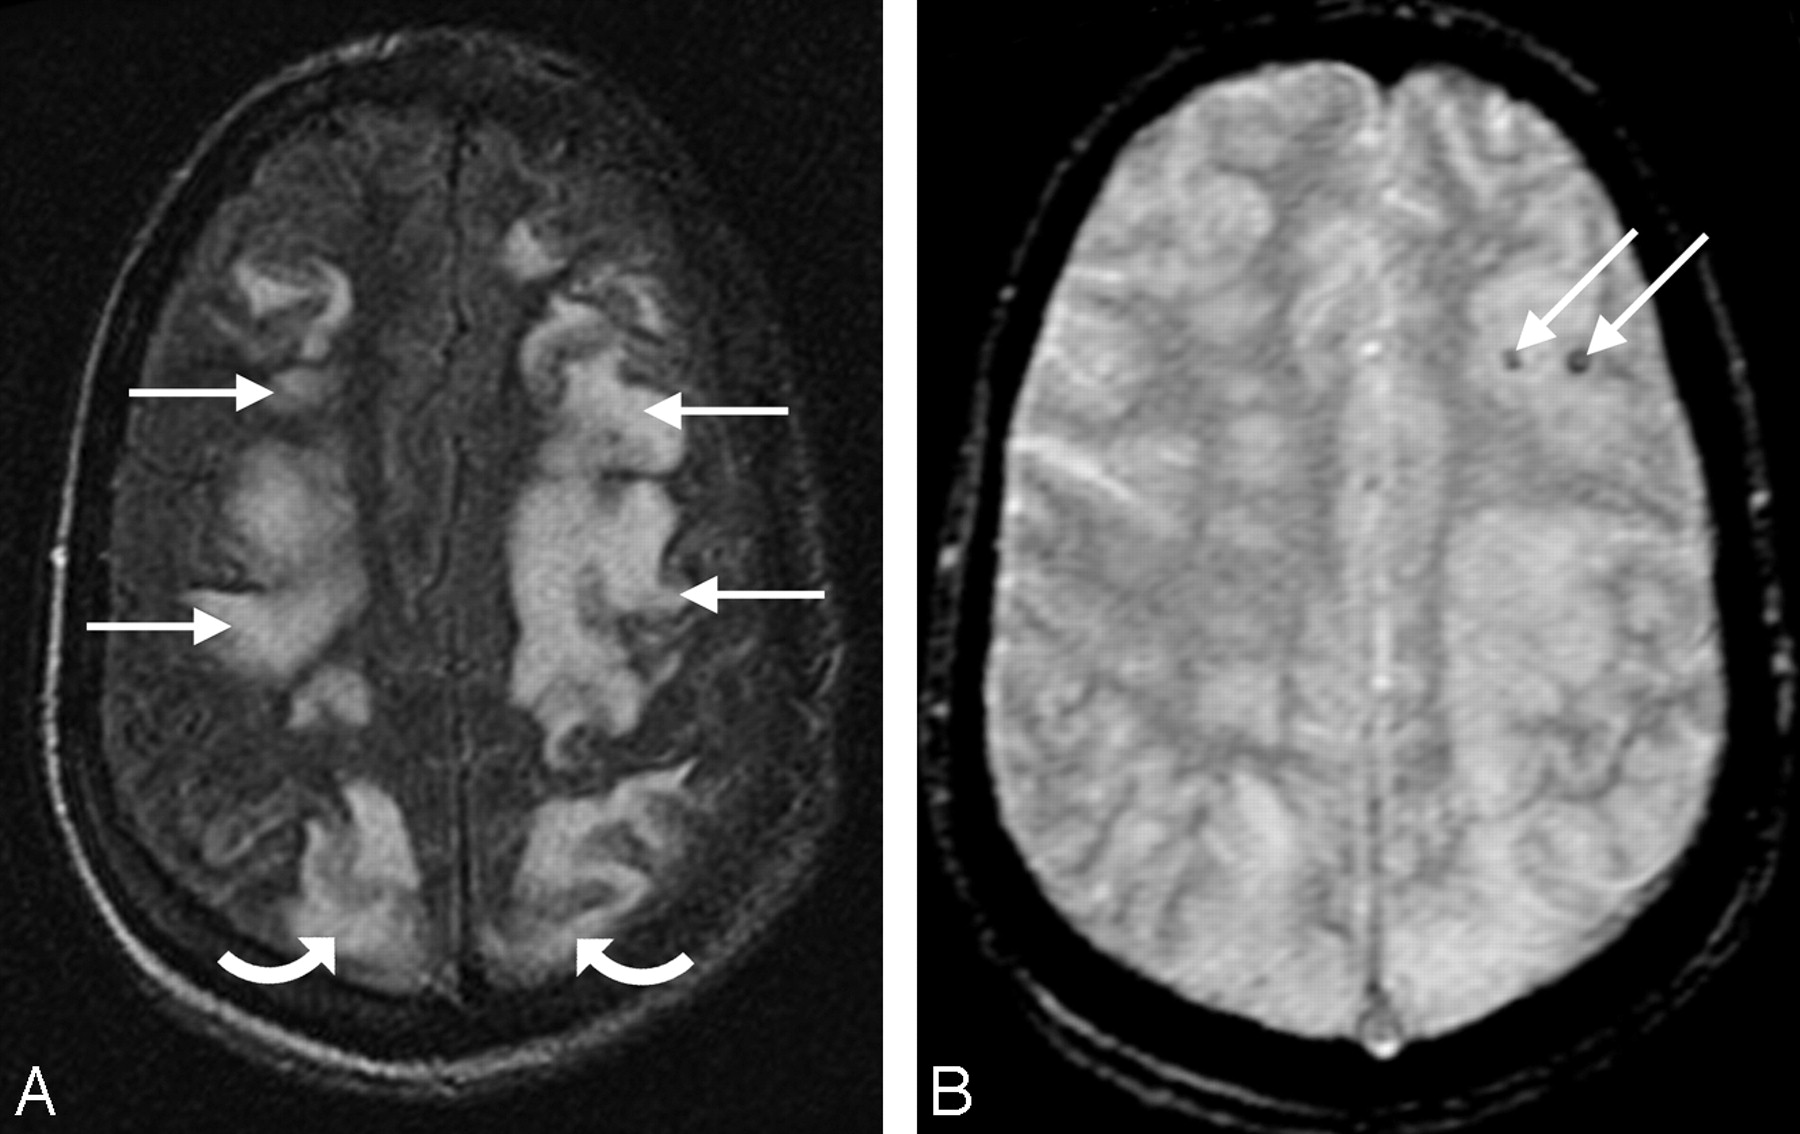

A 27-year-old man with necrotic pneumonia and lung abscess. A, MR FLAIR image demonstrates PRES vasogenic edema in the parietal and frontal lobes (arrows). B, Gradient image demonstrates minute hemorrhages in the left frontal lobe (arrows).